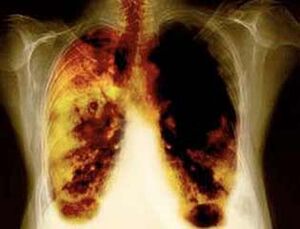

- Réduisez le risque de développer un cancer du poumon et de nombreux autres types de cancer.

- Réduire le risque de développer certaines maladies pulmonaires (par exemple, une maladie pulmonaire obstructive chronique).

- Après 1 à 9 mois, la toux et le manque de respiration ont lieu: les cils (petits cheveux) commencent à traiter le mucus normalement, purifiant les poumons et réduisant le risque d'infection.

- 10 ans après la cessation de la fumée de 40%, la probabilité de cancer du poumon diminue de 40%.